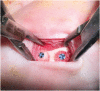

Methods: Twelve New Zealand white rabbits were randomized into 3 treatment groups according to the study period (4, 12, or 24 weeks). Cylindrical specimens measuring 5 mm in diameter and 4.5 mm in thickness were placed directly on the body of the mandible without bone bed decortication, fixed in place with a titanium screw, and covered with a collagen membrane. Histologic and histomorphometric analyses were done using hematoxylin and eosin-stained bone slices. Interfacial shear strength was tested to quantify graft-bone interfacial integrity.

Results: The porous polyethylene graft was observed to integrate with the mandibular bone and exhibited tissue-bridge connections. At all postoperative time points, it was noted that the host tissues had grown deep into the pores of the porous polyethylene in the direction from the interface to the center of the graft. Both fibrovascular tissue and bone were found within the pores, but most bone ingrowth was observed at the graft-mandibular bone interface. Bone ingrowth depth and interfacial shear strength were in the range of 2.76-3.89 mm and 1.11-1.43 MPa, respectively. No significant differences among post-implantation time points were found for tissue ingrowth percentage and interfacial shear strength (P>0.05).